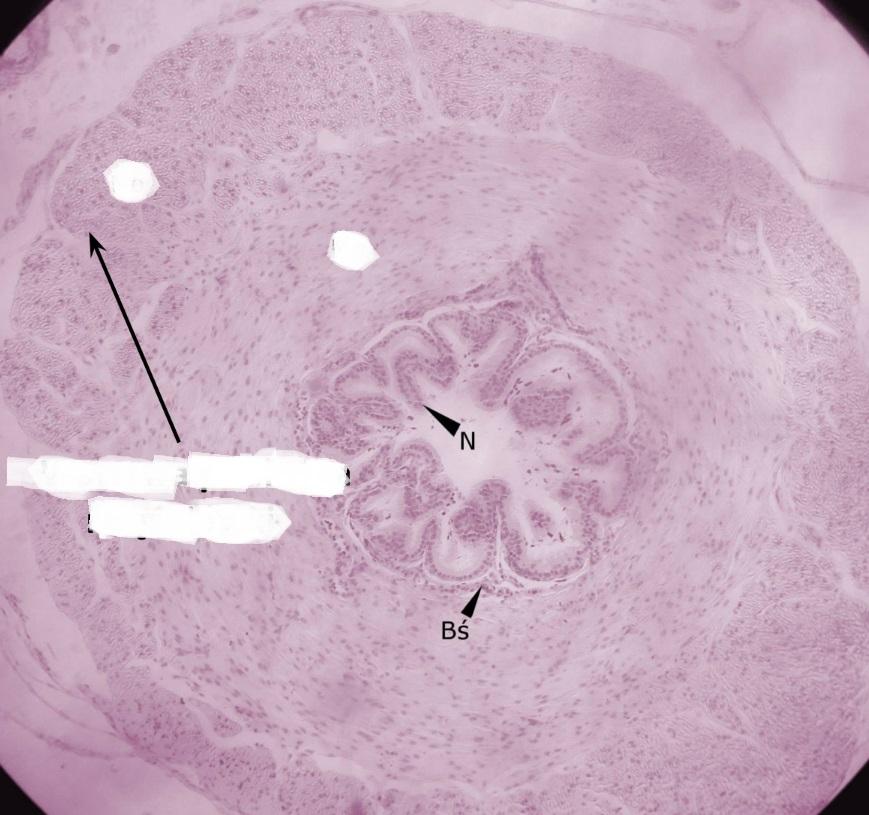

Pytanie 557

pofałdowana błona śluzowa z nabłonkiem dwurzędowym walcowatym (nasieniowód)